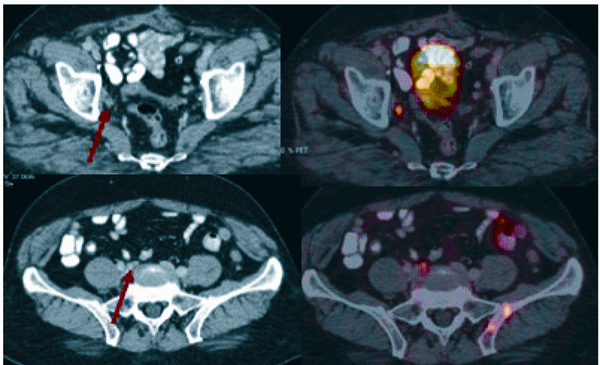

The measurement of PSA level alone is unhelpful in predicting the presence of lymph node metastases for an individual patient. CT and MRI show lower sensitivity (<40 per cent for 10 mm threshold) in PCa nodal staging as they indirectly assess nodal invasion by measuring lymph node diameter and microscopic invasions cannot be detected. PSMA-PET/ CT is invaluable in detecting sub-centimetre sized positive metastatic deposits which would have been reported as reactive, inflammatory or even be considered as non-existent on a conventional CT or MRI report as shown in Figure 5.